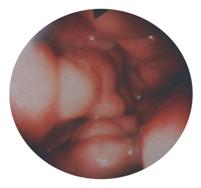

esogastroscopie (examenul cel mai fiabil, care stabileste si gradul evolutiv al varicelor esofagiene - clasificarea Dagradi, cea mai folosita, cuprinde 5 grade evolutive:

gradul I = varice de 1-2 mm largime si 1-2 mm elevatie fata de planul mcoasei, ce apar numai in timpul manevrei Valsalva

gradul II = varice permanente de 2-4 mm largime si 2-4 mm elevatie

gradul III = varice cu dimensiuni de 4-6 mm

gradul IV = varice de 6-8 mm

gradul V = varice care oclud complet lumenul esofagian)

aspect esofagoscopic de varice mari, nodu-

varice esofagiene prin asa-numitul "banding", etc.). lare, tortuoase, cu aspect ocluziv (gradul V)